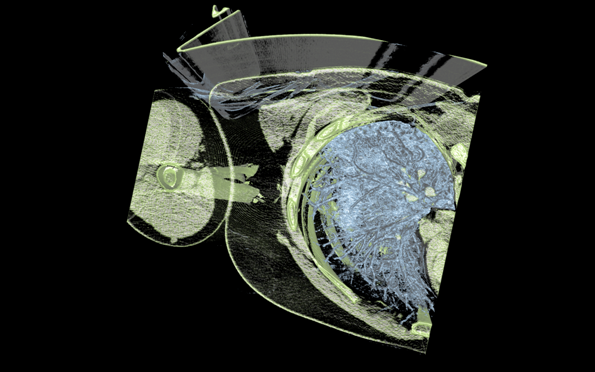

Scan image from the new medical viewset to be introduced in SPECviewperf 13.

SPECviewperf 13 will feature new volume visualization viewsets for energy and medical applications, radically new shaders, and updated viewsets to match more recent versions of the applications on which they are based.